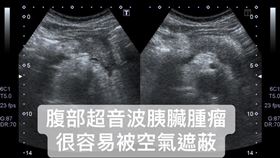

「癌王」胰臟癌早期無症狀?醫師:其實有

胰臟癌被認為是難以對付的「癌王」,不容易早期發現,治...